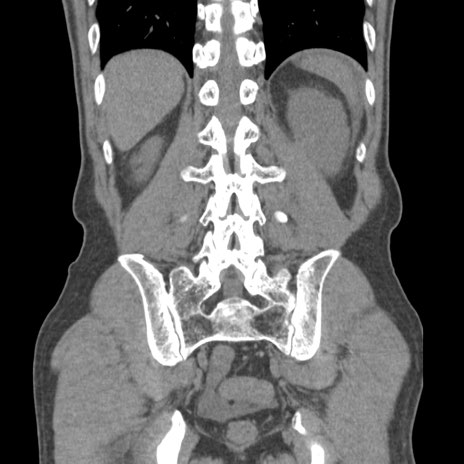

症例56 CT(冠状断像)

横断像